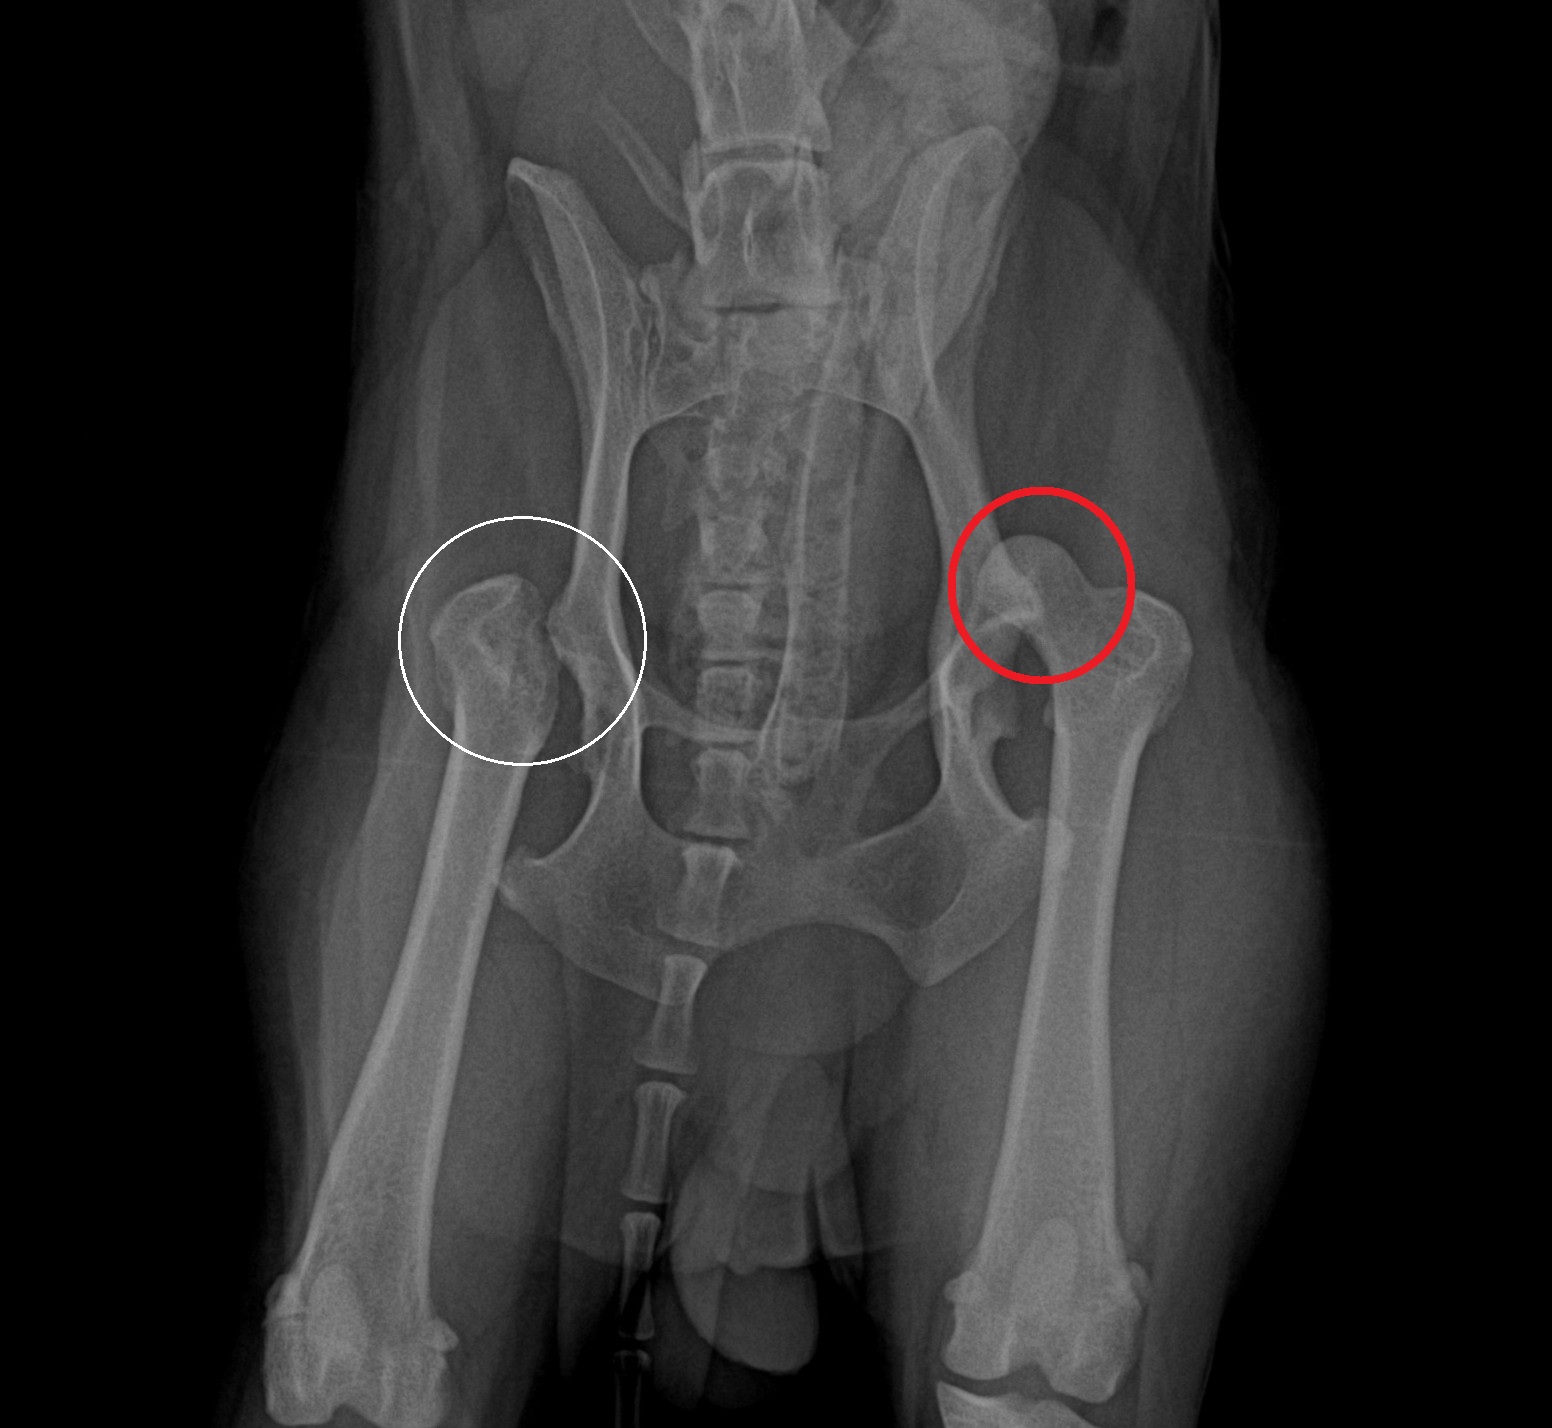

レントゲン検査の結果、左の股関節が脱臼(赤丸)していることが分かりました。

なお、反対側の股関節は以前に脱臼を起こしており、他院にて大腿骨頭切除術(白丸)が行われていました。